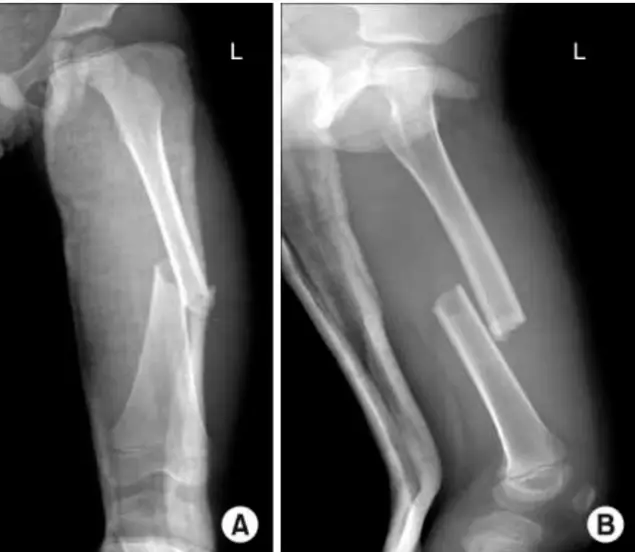

- Site: Shaft tibia â lowerâŻ1/3

- Type: Simple

- Fracture line: Transverse

- Displacements: Lateral & posterior shift; minimal medial & anterior tilt

- Special issues: Joint above not visualized